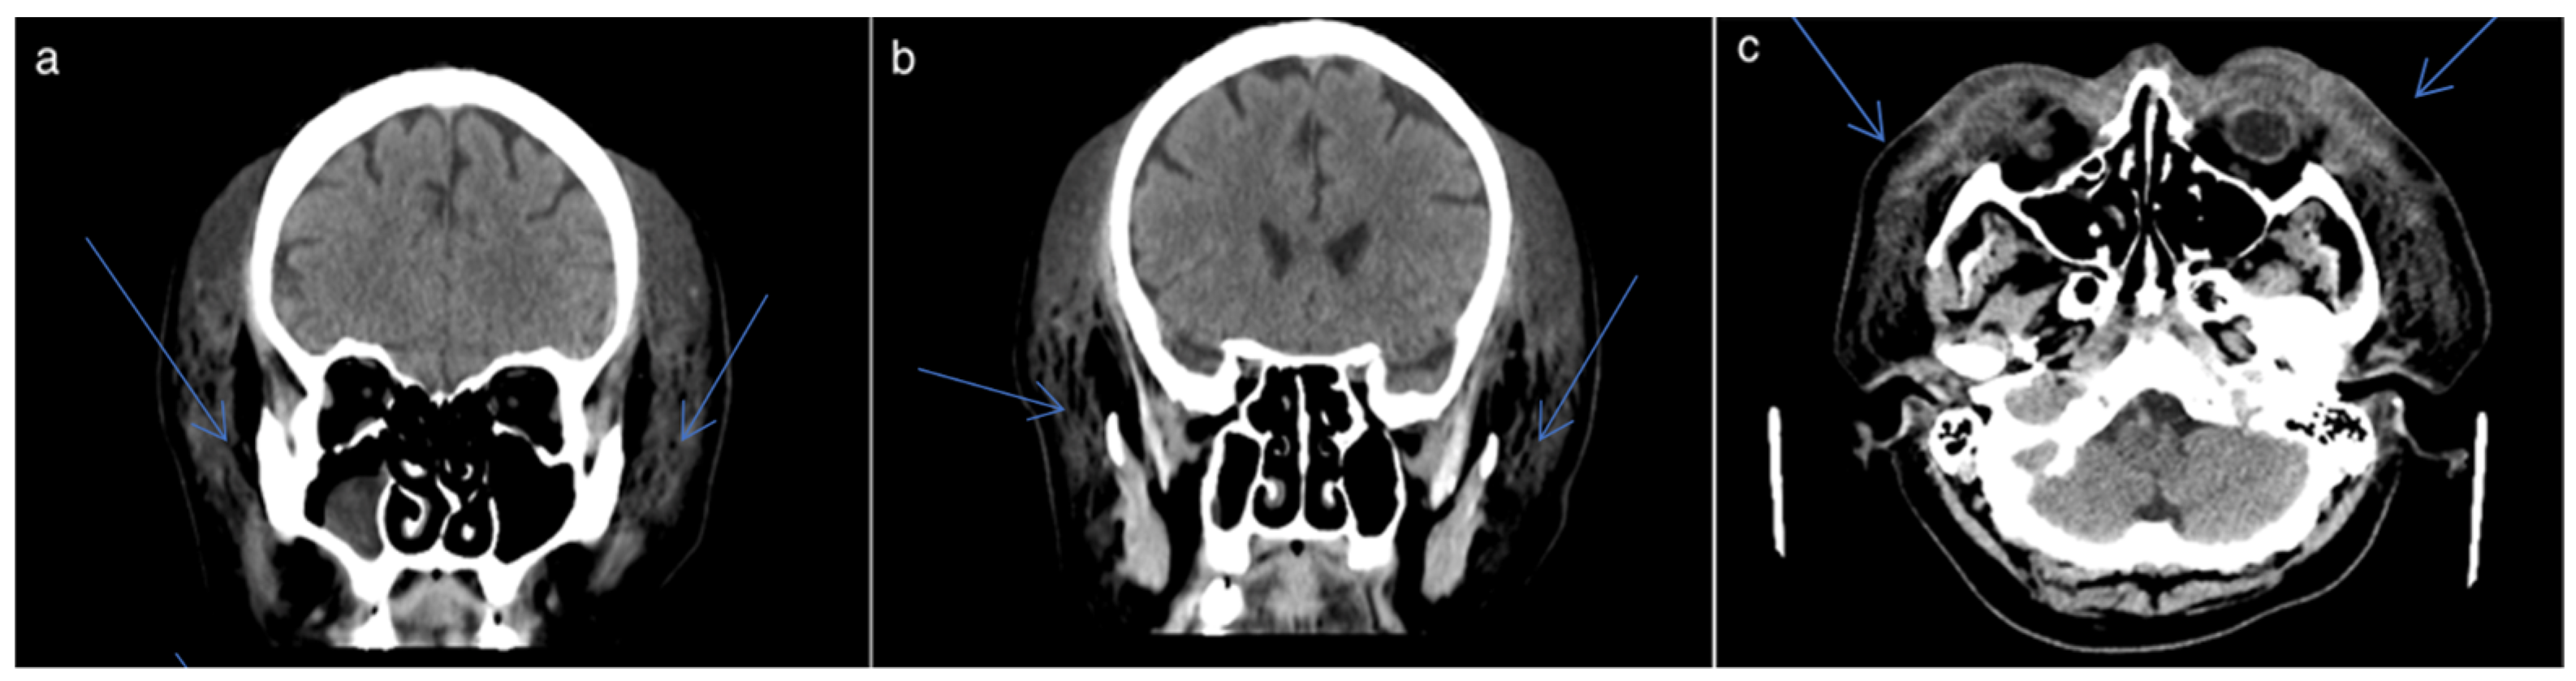

2.1. Clinical Presentation